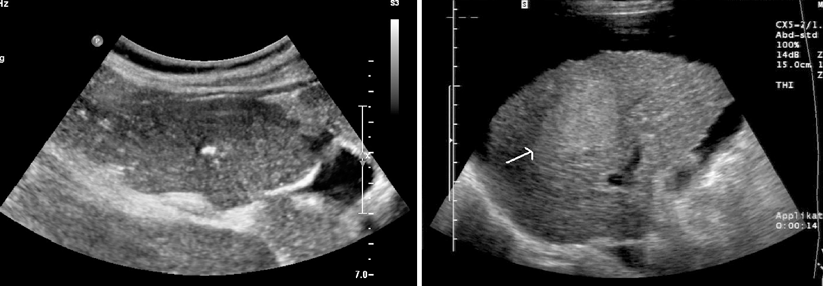

Kontrolle in der MRT nach erfolgreicher Mikrowellen­ablation. Der Tumor nimmt kein Kontrastmittel mehr auf und ist von einer großen Ablationszone (Pfeil) umgeben (links).

Exakte Positionierung der Ablationsantenne (Pfeil) in der MRT (rechts). Kontrolle in der MRT nach erfolgreicher Mikrowellen­ablation. Der Tumor nimmt kein Kontrastmittel mehr auf und ist von einer großen Ablationszone (Pfeil) umgeben (links). Exakte Positionierung der Ablationsantenne (Pfeil) in der MRT (rechts). © Institut für Diagnostische und Interventionelle Radiologie, Medizinische Hochschule Hannover (Professor Dr. Frank Wacker)